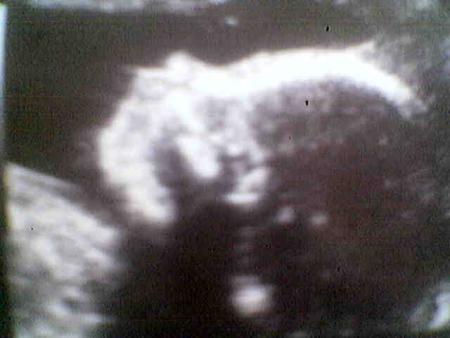

profil de bb au 5eme mois